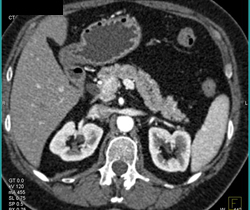

Pancreatic Cancer With Carcinomatosis and Invasion of PV/SMV